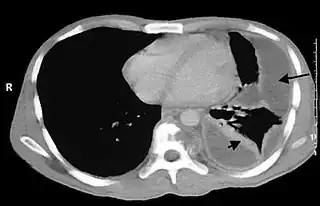

![]() Empiema pleural en tórax. | ||